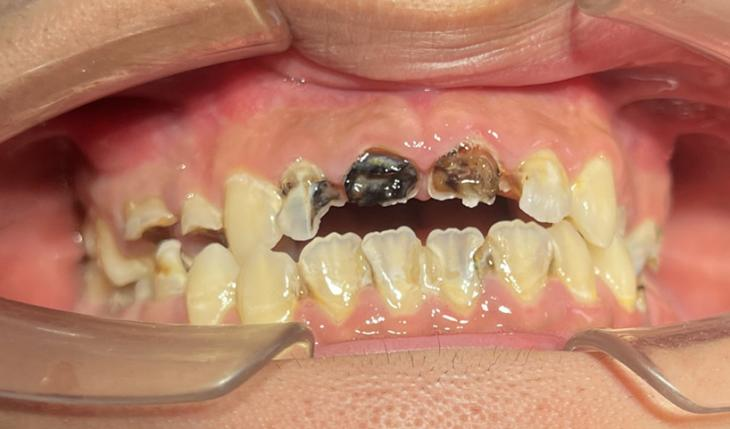

近日,广州市花都区人民医院口腔科通过规范的诊疗流程,为一名18岁男孩完成牙齿“蜕变”,让其重拾自信笑容。

这名男孩就诊时满口黑牙,颜值大打折扣。广州市花都区人民医院口腔科结合放射检查、内科治疗、外科干预及修复重建等诊疗环节,制定了“拍片检查—牙周治疗—拔牙—根管治疗—桩冠修复”的系统性方案,后续还将为其缺失牙进行种植修复。